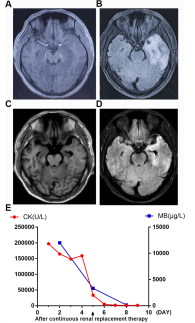

血常规显示Mb(12000 g/L,正常<140 g/L)和CK(197159 U/L,正常38-174 U/L),GFR(肾小球滤过率)低,肾功能受损(26 ml/min,正常90-120 ml/min)。白细胞、C反应蛋白(CRP)、血沉(ESR)、肝功能中度升高。其他指标包括ANCA/GBM、肿瘤标志物和甲状腺功能、血糖、电解质、性传播疾病(包括HIV)均在正常范围内。此外,脑脊液(CSF)检查显示蛋白质水平升高(0.92 g/L,正常0.15–0.45 g/L)和白细胞轻度增加(12.9*106/L,正常<8*106/L),表明病毒性脑炎感染的可能性很高。左侧颞叶、海马和岛叶肿胀,在MRI图像上显示出高T2信号(图1a和b)。

在住院的3周内,患者每隔8小时服用300mg阿昔洛韦进行抗病毒治疗,同时服用300mg奥卡西平和500mg丙戊酸钠进行抗癫痫治疗,每天两次。此外,患者还服用了10mg地塞米松来控制炎症。由于Mb和CK含量极高,因此使用1000毫升生理盐水和维持8小时的单次血液透析作为补液治疗(图1e)。治疗3周后完全缓解。出院后,患者连续口服抗病毒药物(阿昔洛韦,100mg,一天三次)和抗癫痫药(丙戊酸钠,500mg,一天两次)4周,之后返回进行随访。随访时的MRI图像显示颅内病变明显改善(图1c和d),脑脊液样本的病毒PCR结果显示HSV-1和HSV-2呈阴性。

图1.治疗前后MRI图像及MB、CK含量的变化。a、b左颞叶、海马、岛叶MRI表现为肿胀,住院时可见T2高信号。随访时的c和d MRI图像显示颅内病变明显改善。e. 血液透析治疗前后肌红蛋白、肌酸激酶的变化趋势。MK,肌红蛋白。CK,肌酸激酶